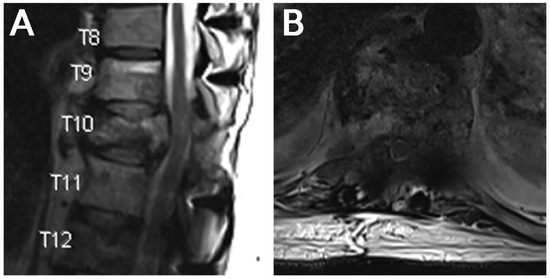

Using Endoscopic Approaches in the Surgical Management of Spinal Metastatic Disease

Patients with spinal metastasis often benefit from surgical intervention for debulking to improve neurologic deficits, reduce spinal cord or root compression, and ameliorate pain. Traditionally, large, open fusions have been used to achieve adequate decompression of neural structures. These types of interventions are frequently associated with significant blood loss, prolonged hospitalizations, and increased risk of surgery-related complications, which can delay postoperative chemotherapy and radiation therapies. Endoscopic spine approaches allow access to the spinal cord and nerve roots with minimal soft tissue disruption, which has been shown to reduce risks associated with open surgery in other contexts. Furthermore, the smaller incision, reduced blood loss, ability to position incisions away from radiation fields, and lower risk profile in high-risk patients may provide an effective solution to spinal metastases in appropriately selected cases. Here, we present two cases of spinal metastases successfully managed with spinal endoscopy and recommend the consideration of this approach for similar scenarios. Full article